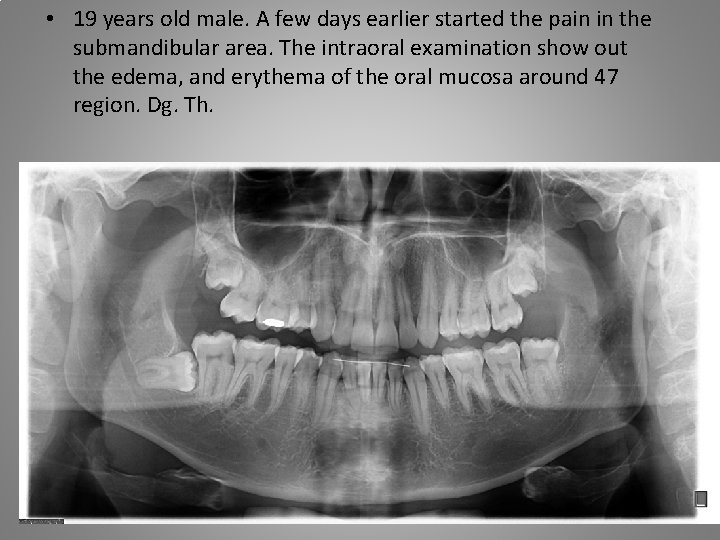

• 19 years old male. A few days earlier started the pain in the submandibular area. The intraoral examination show out the edema, and erythema of the oral mucosa around 47 region. Dg. Th.